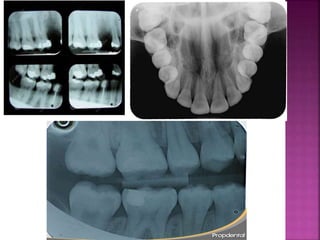

ANALISIS

RADIOGRAFICA